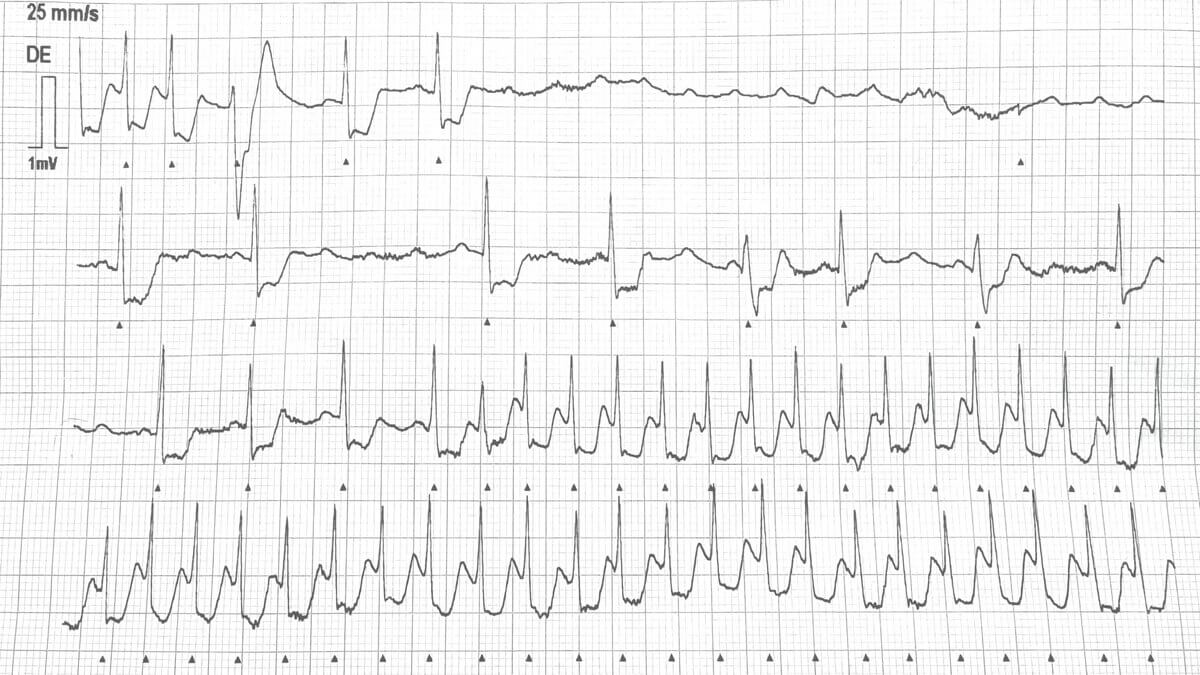

Adenosin ist als Arzneistoff zur Beendigung supraventrikulärer Tachykardien, z.B. einer AV-Knoten-Reentrytachykardie (AVNRT) und AVRT indiziert. Es blockiert die AV-Überleitung. Darüber hinaus wird Adenosin diagnostisch zur Differenzierung supraventrikulärer Tachykardien eingesetzt, da die kurzfristige AV-Blockade Vorhofaktivität (z.B. bei Vorhofflattern) demaskieren kann.

Adenosin darf nur unter intensivmedizinischer Überwachung und Reanimationsbereitschaft verabreicht werden. Eine kontinuierliche EKG-Überwachung ist zwingend notwendig, um eventuelle Arrhythmien sofort erkennen und gegebenenfalls intervenieren zu können.

Bei Patienten mit Vorhof- oder Kammertachykardien oder Tachykardien, die auf Vorhofflimmern oder -flattern zurückzuführen sind, hat sich Adenosin als wirkungslos erwiesen. Allerdings kann es diagnostisch hilfreich sein, dass es durch die AV-Blockade die zugrunde liegende atriale Aktivität sichtbar machen kann.